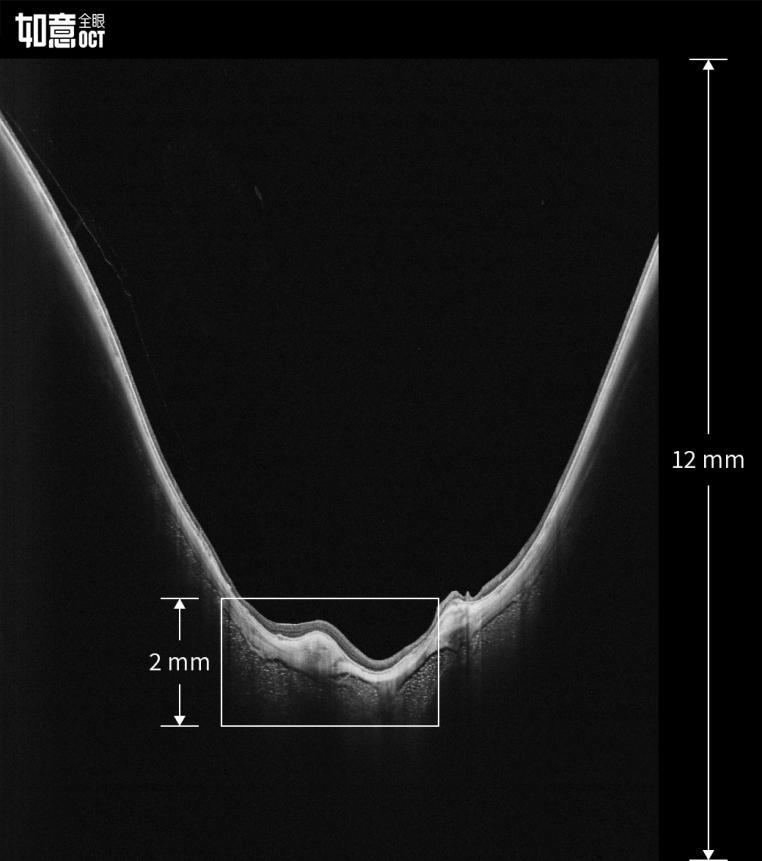

4、超深度成像

与上一代传统技术相比,全新的如意全眼OCT成像深度提升了6倍,对于以往无法完整检查的高度近视、视网膜脱离等病变也能提供完整的病变信息。

视微如意全眼OCT12mm超级深度成像